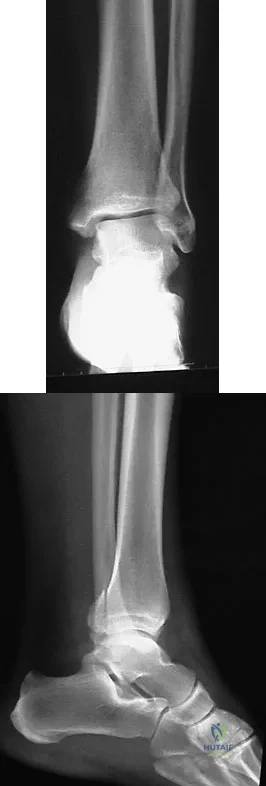

Figures 5a and 5b show the radiographs of a 56-year-old man who was seen in the emergency department following a twisting injury to his left ankle. Examination in your office 3 days later reveals marked swelling and diffuse tenderness to palpation about the ankle and leg. What is the next most appropriate step in management?

Explanation

A 35-year-old man who snowboards sustained the injury shown in Figures 4a through 4c. What is the mechanism of injury?

Explanation